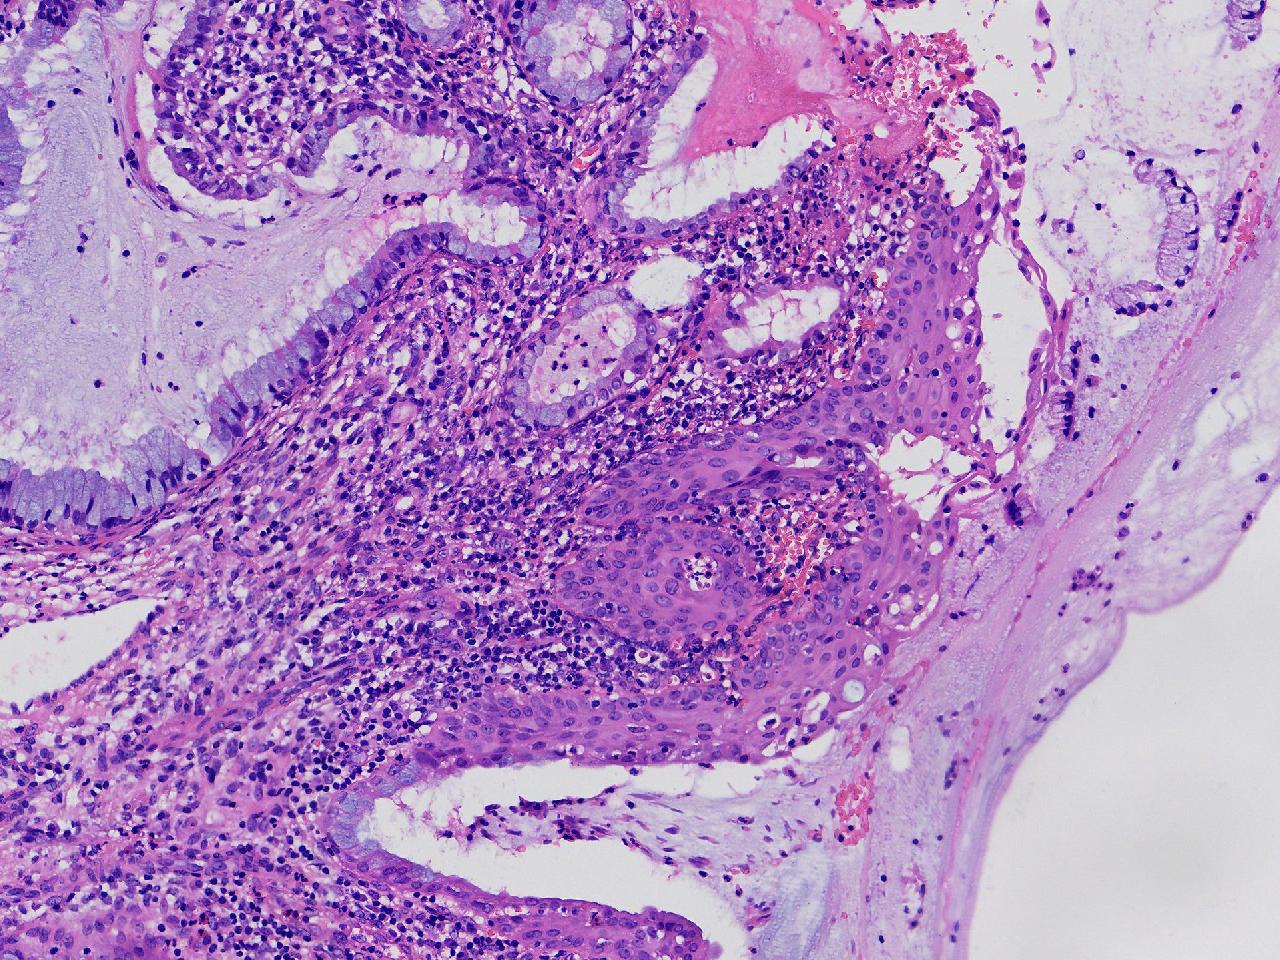

CIN1级? CIN2级?

女,41岁,宫颈活检,HPV16(+)

宫颈多点活检。

灰白色不整形软组织多块。

图4

慢性宫颈炎伴鳞化,建议定期复诊

慢性炎,储备细胞增生伴鳞化,